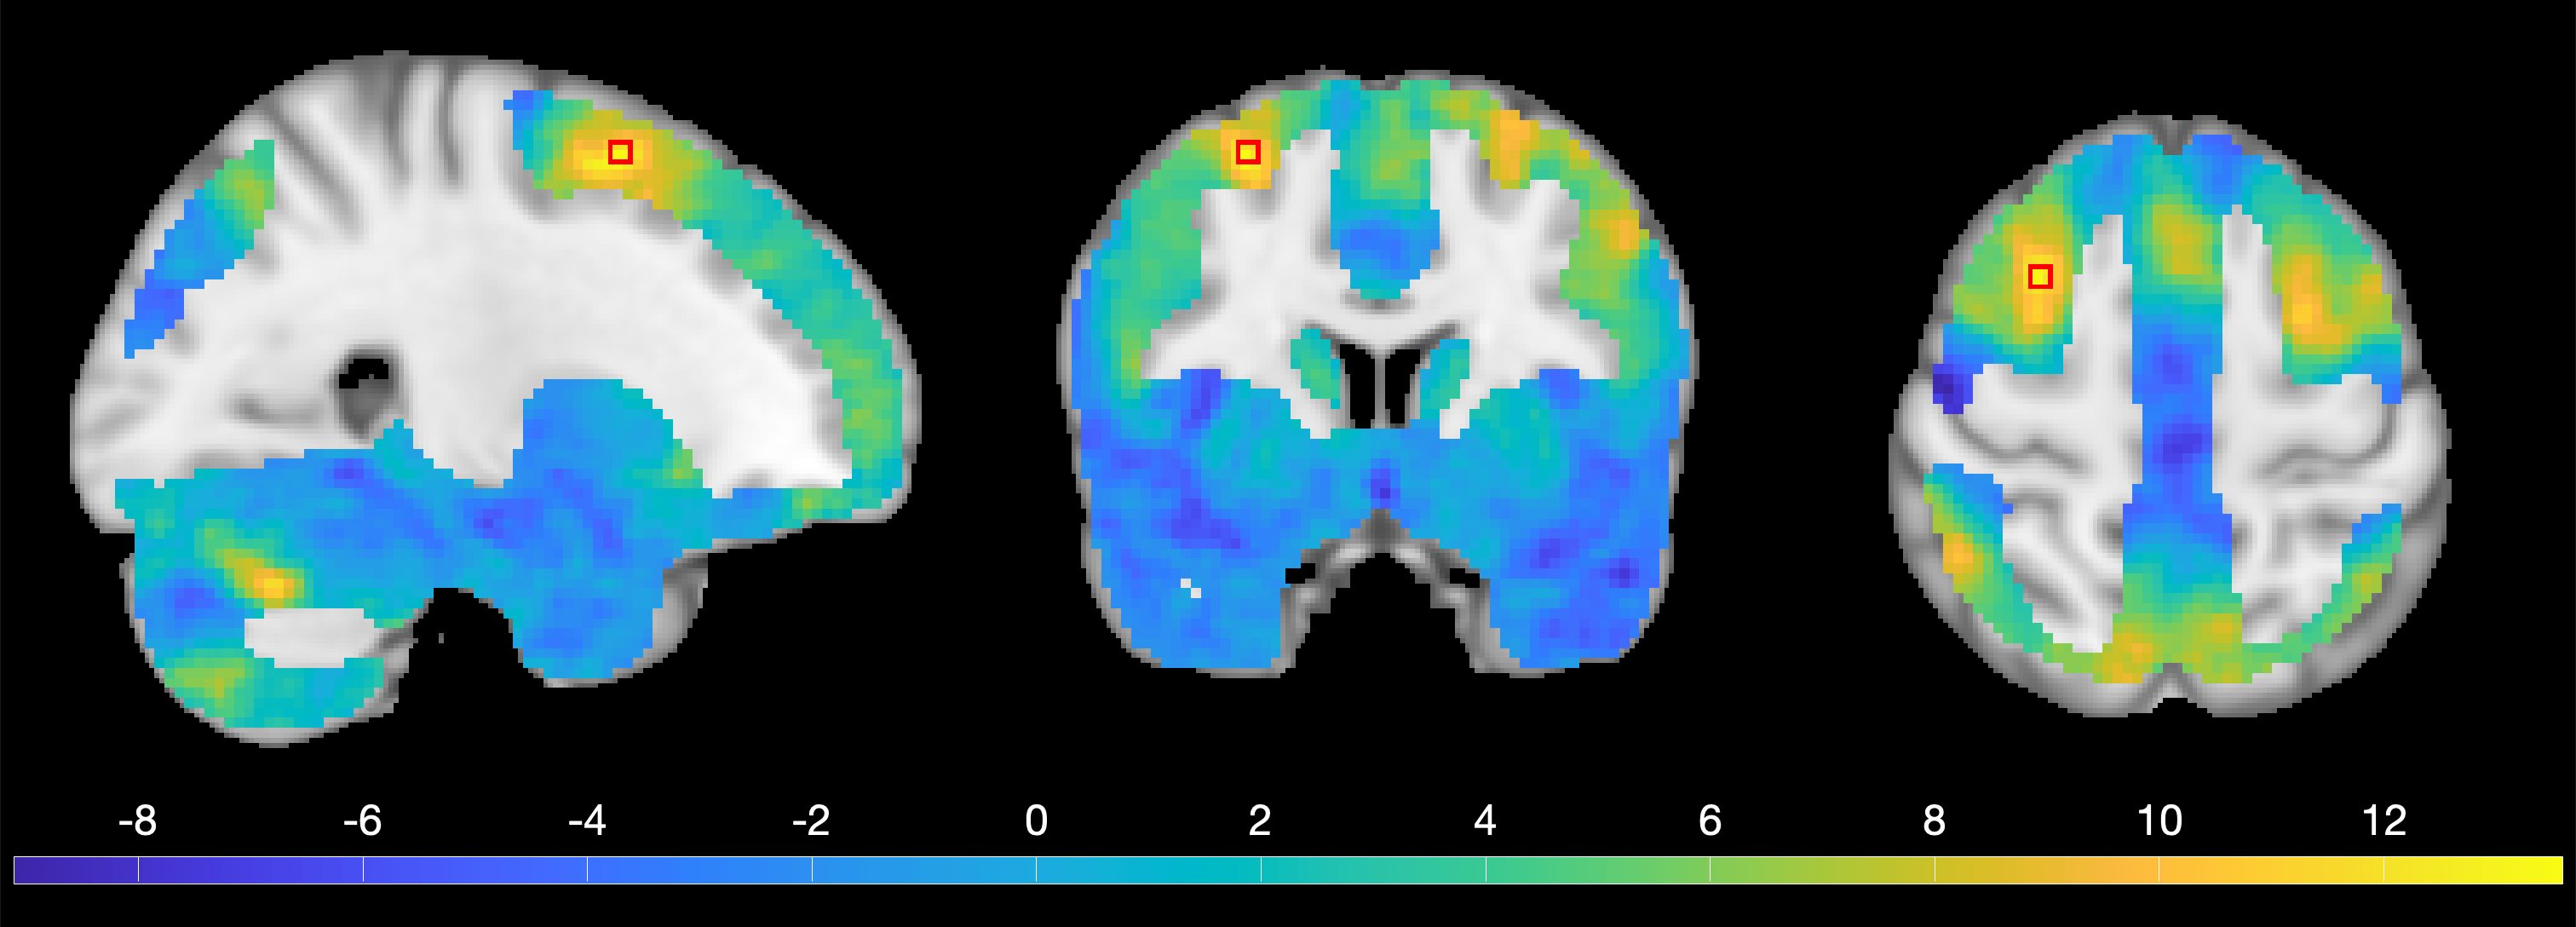

5 HCP Task fMRI Results

We evaluate the methods on 80 unrelated subjects of the Human Connectome Project (HCP) by testing one of the working memory contrasts. Specifically, we focus on the average contrasts of 2-back and 0-back tasks (Davenport and Nichols, 2020). Since N-back task is commonly used to measure working memory, and N can be adjusted for task difficulty, such contrasts help to identify the brain regions supporting working memory (Kirchner, 1958). To ensure that the assumption of stationarity is reasonable we restrict to a mask of the gray matter on which the smoothness can be assumed to be constant (personal communication with Thomas E. Nichols), see e.g. Supplementary Figure 19 of Eklund et al. (2016).

We perform the peak inference by computing the one-sample -statistics at voxel level and applying MCDLM for -fields to calculate -values for 1101 peaks that we found in image. We use both MCDLM based on multivariate -distribution and Gaussianization transformation method described in Section 2.4 for the calculation. The isotropy assumption is too strict as we observe three different correlations, 0.86 (FWHM = 3.06), 0.88 (FWHM = 3.27) and 0.85 (FWHM = 2.87) in the horizontal, vertical and longitudinal directions, respectively. Based on our simulations we would expect continuous RFT to be conservative in this setting due to the low smoothness of this data and since it does not work well for -statistics. Instead this setting is ideal for the use of MCDLM with the estimated neighborhood covariance matrix. We compare the results of both approaches applied to this dataset.

The largest peak has a -statistic value of 13.59. Figure 10 shows slices in different directions through one-sample -statistic corresponding to this location. This peak is located within the medial prefrontal cortex, which is an area commonly associated with working memory (Euston et al., 2012; Perlstein et al., 2002). Using the one-sample version of MCDLM defined in Section 2.4 we calculate a -value of . Instead using the faster but slightly less accurate Gaussianized version of MCDLM we obtain a -value of . It is worth noting that, as MCDLM is a computation-based method, there is no closed-form function to calculate -values across the entire real domain. When the -statistic is extremely large, determining the exact -value requires a large number of samples, making the process computationally intensive. In such case, we conclude that the -value is smaller than the minimum value obtained from the empirical distribution in our Monte Carlo experiments.